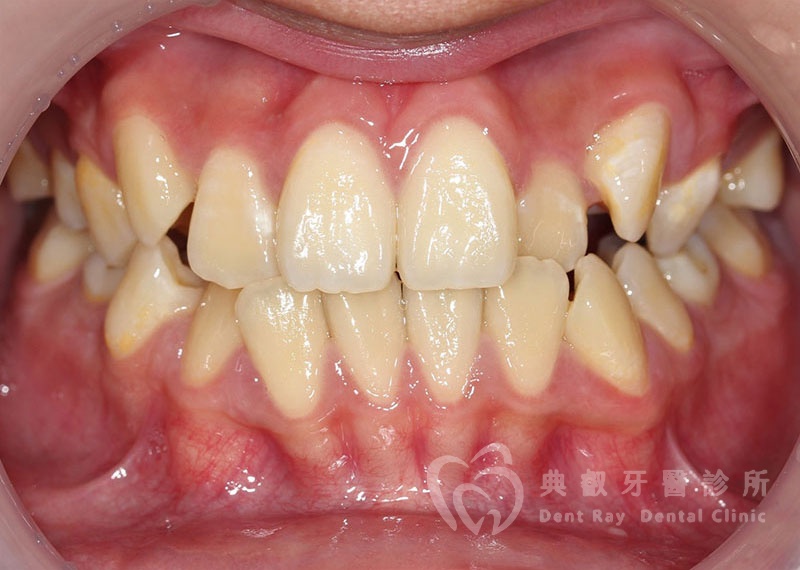

排列擁擠案例一

Before

After